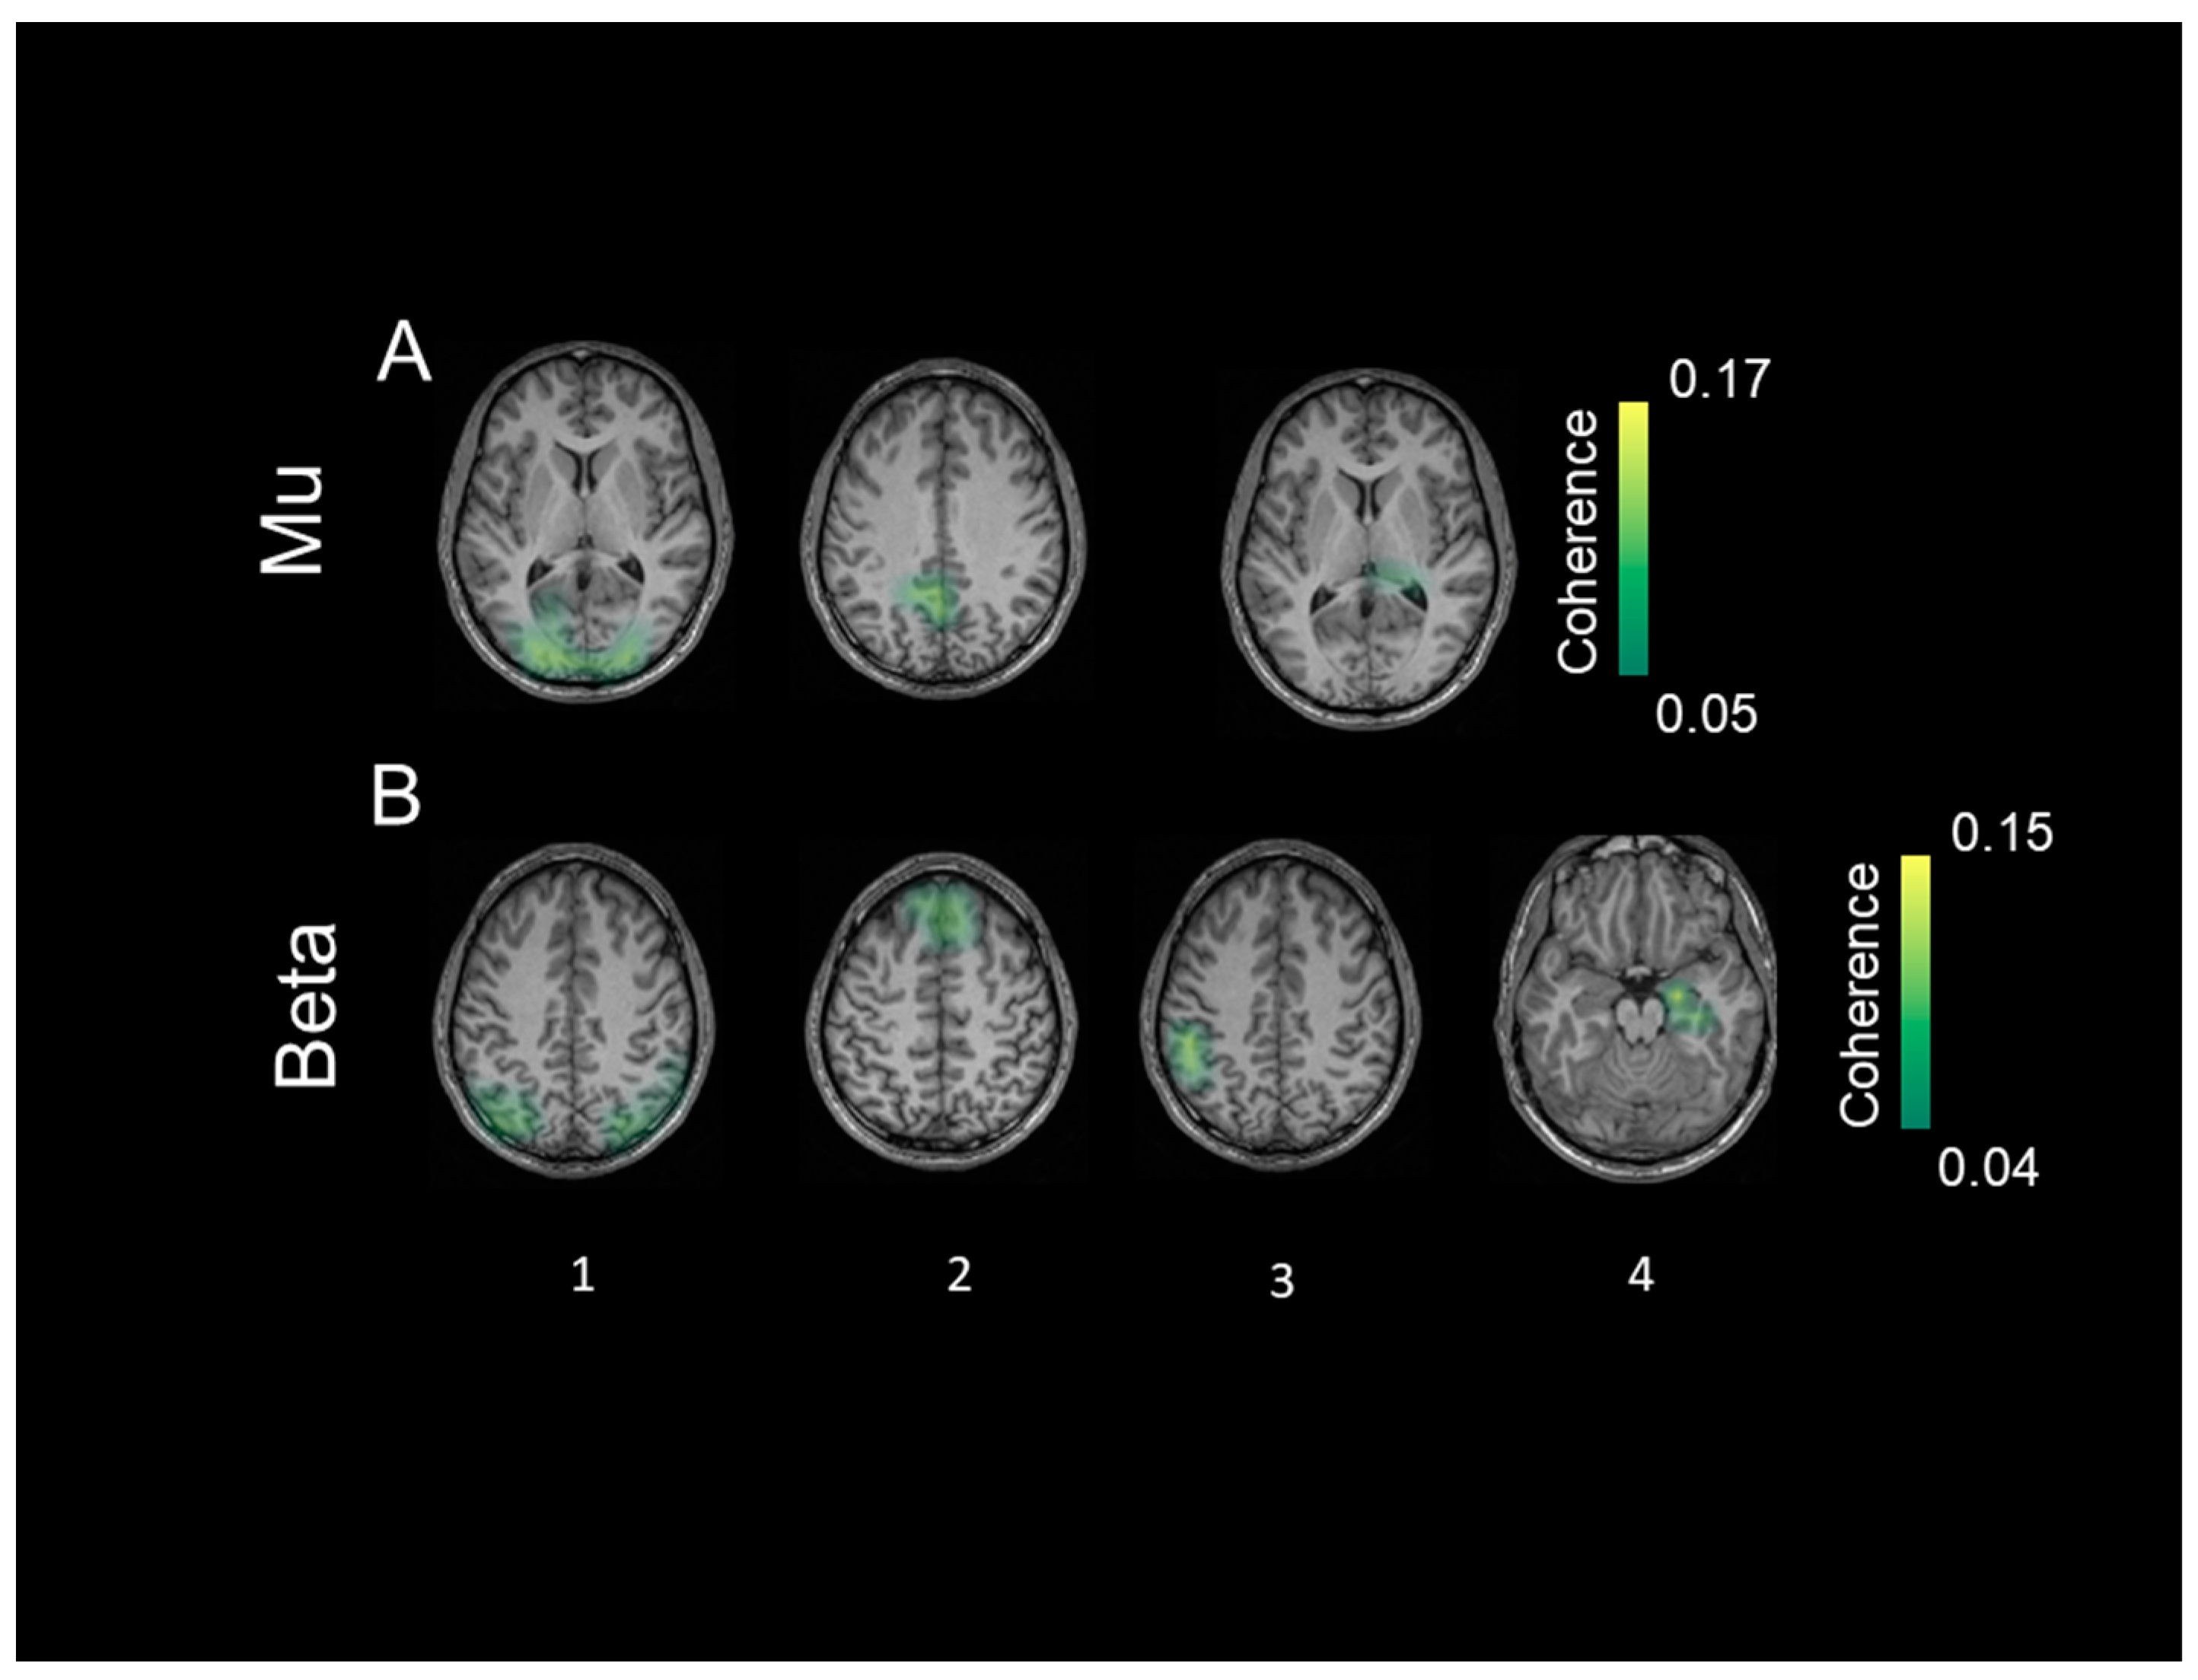

3.4. Coherent Sources

With respect to coherent sources in TDC, mu activity (Figure 5A) was represented by bilateral sources in the visual cortex (source 1), inferior temporal cortex (source 2), parietal cortex (source 3), inferior frontal gyrus (source 4), and putamen (source 5). Coherent sources generating mu activity in individuals with ASD (Figure 6A) were located in the bilateral visual cortex (source 1), posterior cingulate cortex (source 2), and thalamus (source 3).

Figure 5.

The identified coherent sources from typically developing controls separately for the mu frequency (8–12 Hz) in (A) and low-beta frequency (13–20 Hz) in (B). The first source indicates strongest power at each of the frequency bands respectively followed by the other identified significant sources. The color bar shows the significance threshold for identifying 0.05 for mu and 0.04 for low beta frequency.

Figure 6.

The identified coherent sources from the group with autism spectrum disorder separately for the mu frequency (8–12 Hz) in (A) and low beta frequency (13–20 Hz) in (B). The first source indicates strongest power at each of the frequency bands respectively followed by the other identified significant sources. The color bar shows the significance threshold for identifying 0.03 for mu and 0.04 for low beta frequency.

Beta activity (Figure 5B) in the TDC group was associated with bilateral sources in the inferior parietal cortex (source 1), fusiform gyrus (source 2), insula (source 3), medial prefrontal cortex (source 4), and caudate nuclei (source 5). In individuals with ASD, bilateral sources in the inferior parietal cortex (source 1) and medial prefrontal cortex (source 2) as well as left post-central gyrus (source 3), and right hippocampus (source 4) elicited beta activity (Figure 6B).

All identified sources within subject surrogate analyses were statistically significant in the Monte Carlo random permutation test across all subjects per group. The sources identified in each subject survived the surrogate analyses with a significance threshold of (p = 0.002; Cohen’s d = 0.98). The mean coherence values (representing total interaction strength between sources) was stronger in TDC compared to ASD both for the mu (p = 0.0002; Cohen’s d = 0.94) and beta (p = 0.0003; Cohen’s d = 0.88) frequencies.